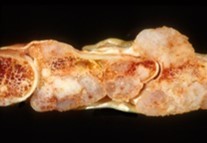

Figure 2.Enchondroma delineating a glistening, grey/white cut surface with an encapsulated, well circumscribed tumour 11.

Figure 3.Enchondroma exhibiting a nodular, encapsulated, well circumscribed, lobulated appearance 12.